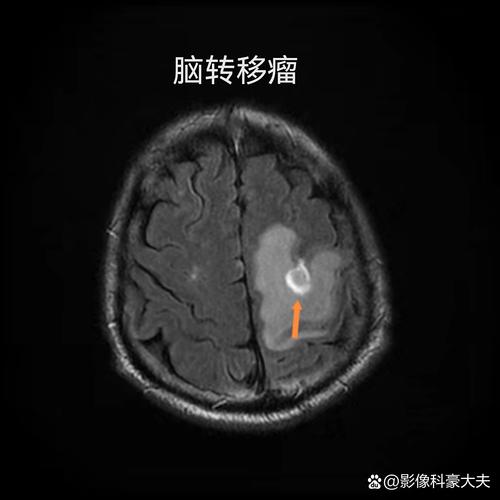

CT还可以帮助排除脑肿瘤、硬膜下血肿、脑脓肿等其他可能导致类似症状的疾病。